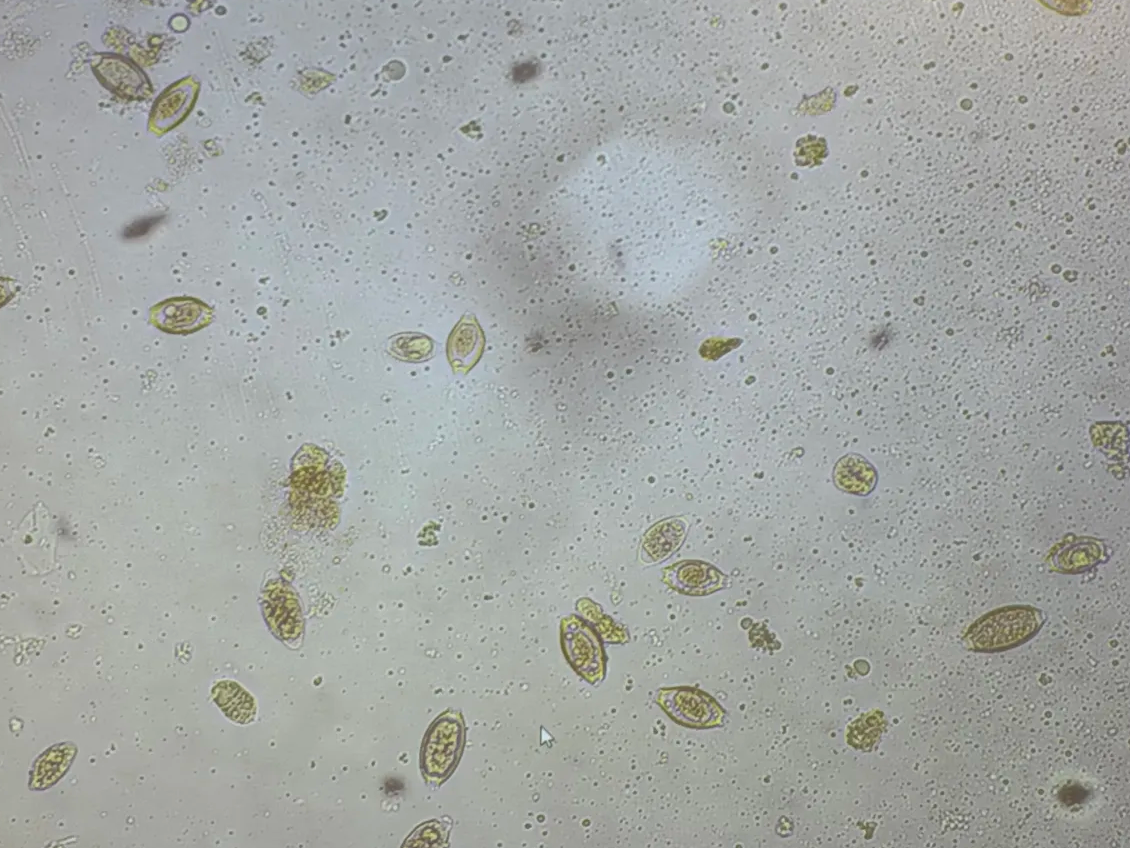

in human and animal stool

abdomen cramps, diarrhea, anorexia

worldwide, common in tropics, outbreaks in North America

history of eating stawrberriy

Cyclospora cayetanensis

oocyst in feces

Cyclosporiasis

fecal/oral transmission